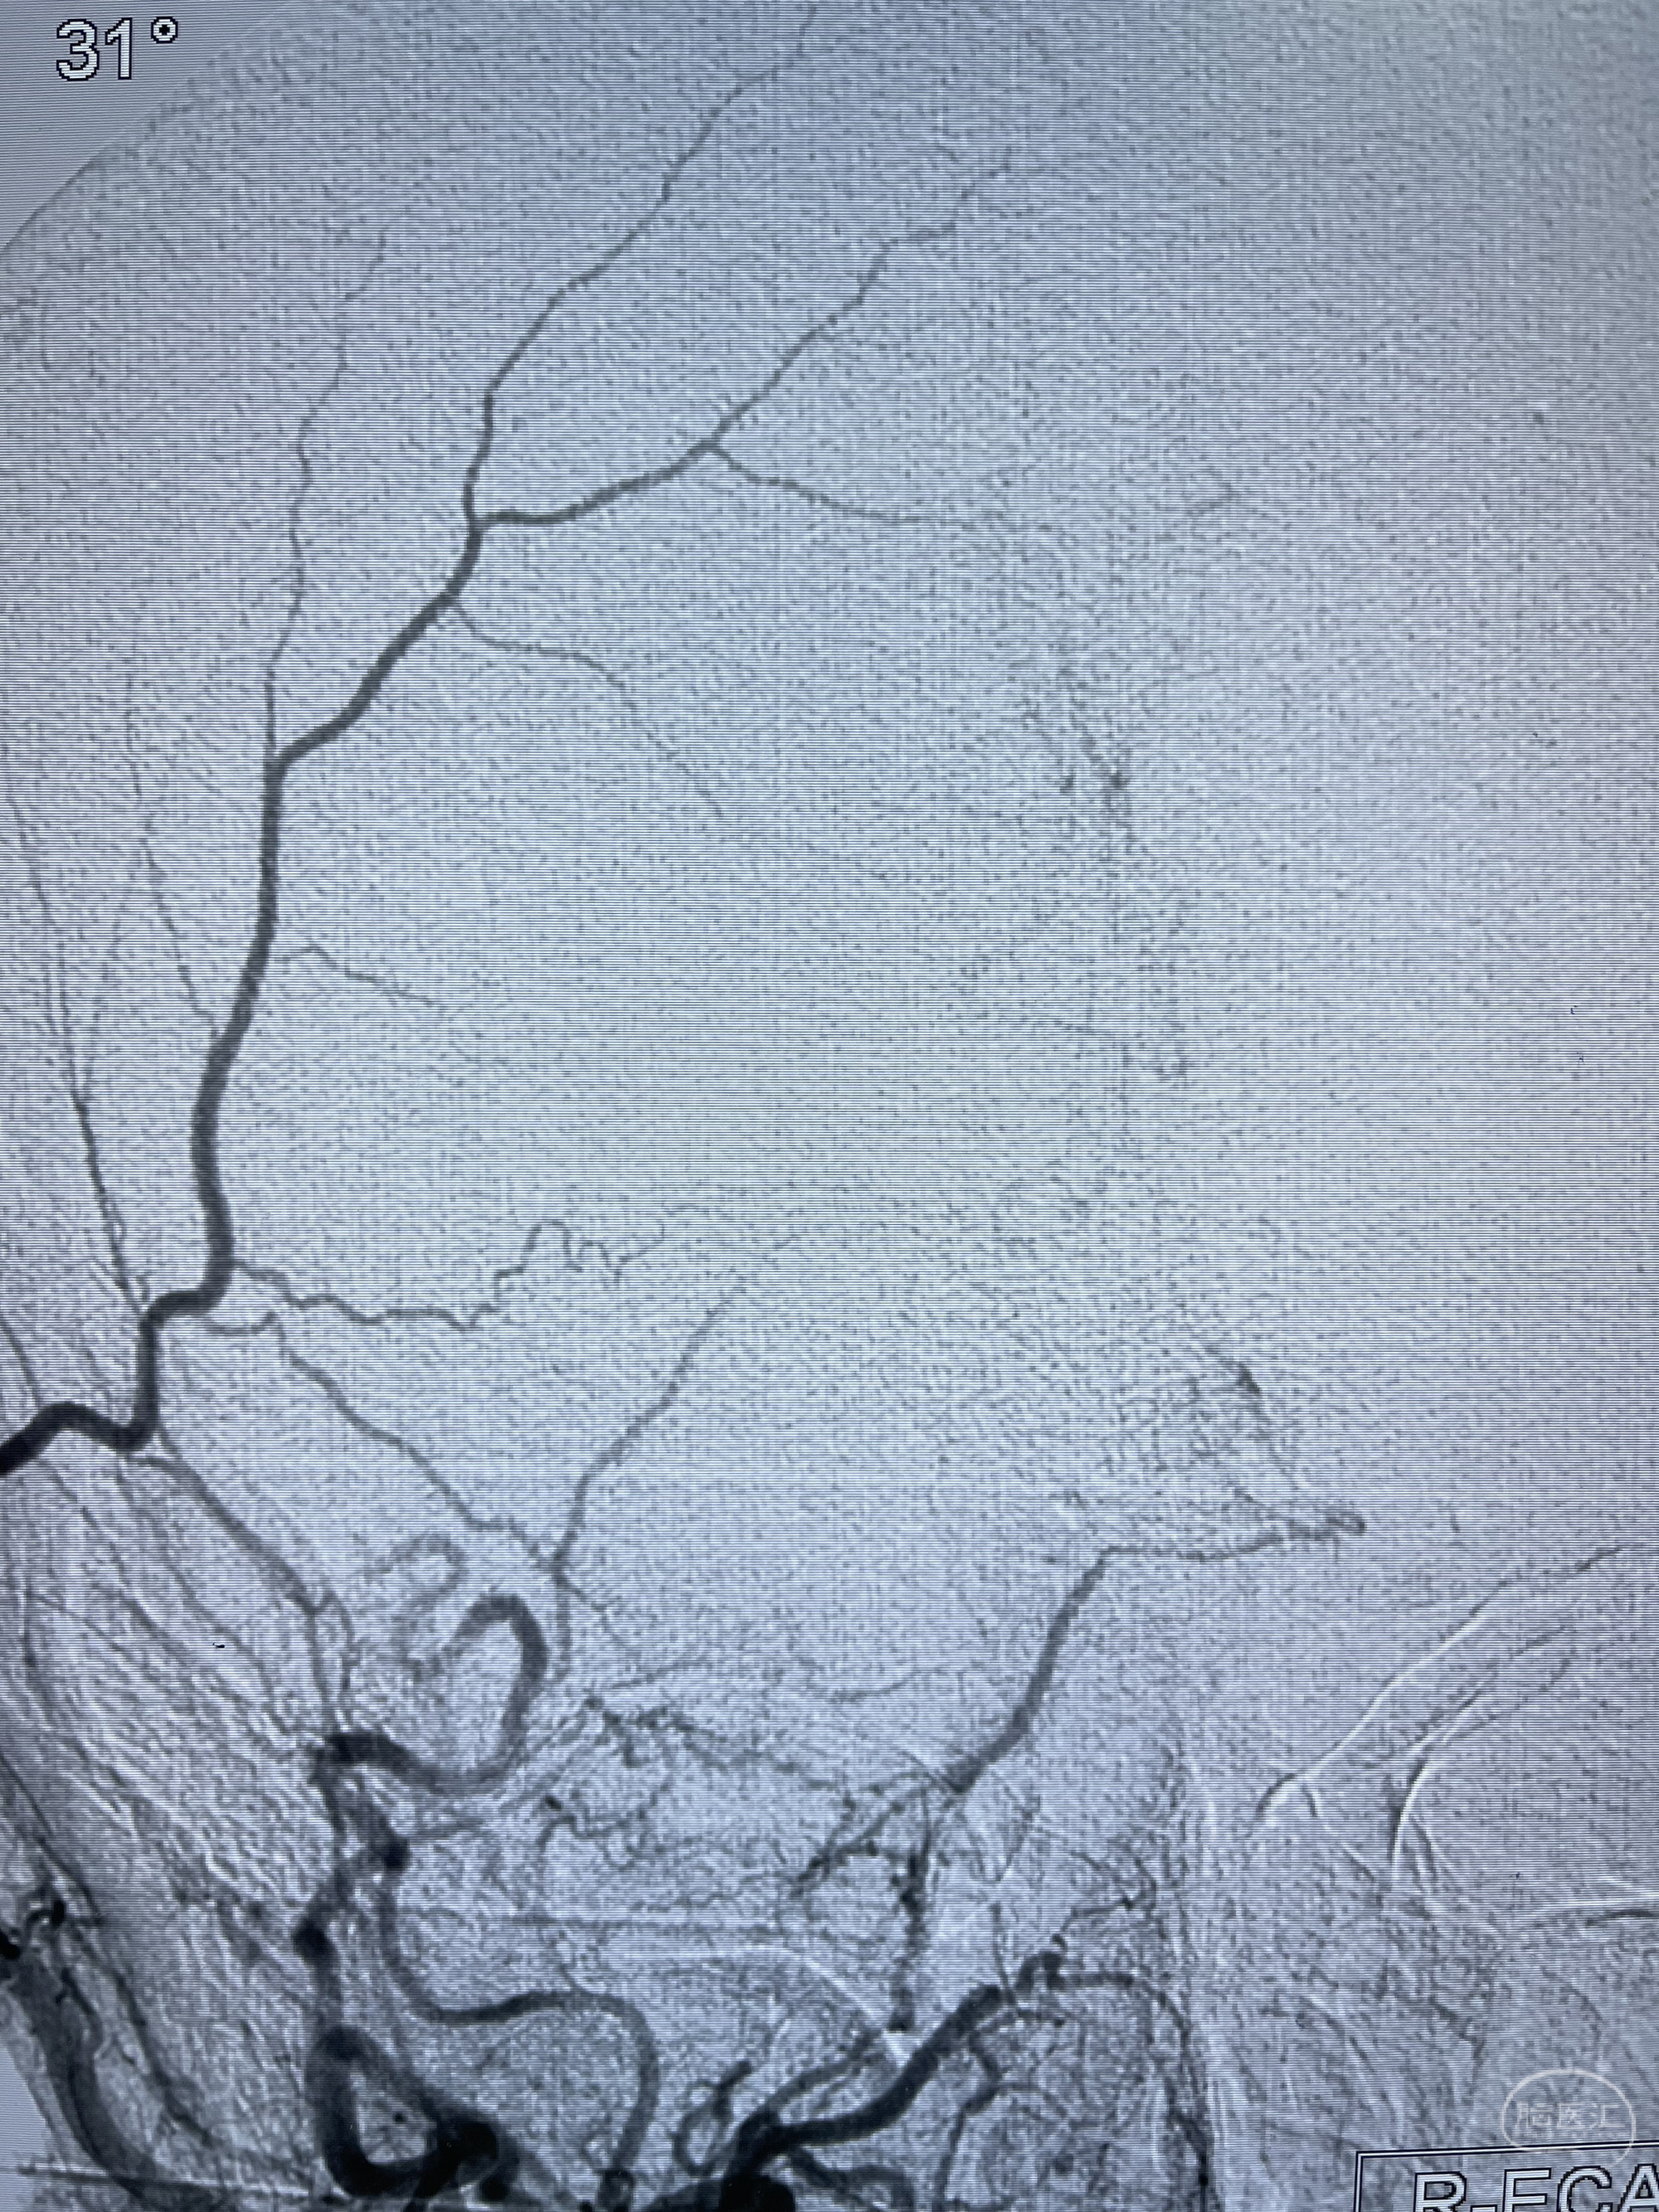

脑血管造影2023.03.06:右侧颈内动脉颈段至岩骨段闭塞,可见后后循环通过原始三叉动脉吻合代偿至海绵窦段,后交通区可见囊状造影剂填充影,左侧锁骨下动脉呈“残端”改变,呈“右侧颈总动脉支架成形术后改变”,支架内血流通畅,可见后交通吻合显影至左侧大脑后动脉,并可见左枕动脉吻合椎动脉至锁骨下动脉

1.右侧颈内动脉及左侧锁骨下动脉闭塞

4.右侧颈外动脉可见经由右侧脑膜中动脉吻合显影右侧眼动脉及颈内动脉

1.箭头处为右侧颈内动脉后交通动脉处重度狭窄,狭窄前壁为不规则动脉瘤;

2.狭窄远端颈内动脉由左侧颈内动脉经左侧后交通动脉—基底动脉顶—右侧后交通—右侧颈内动脉—右侧大脑中动脉途径代偿